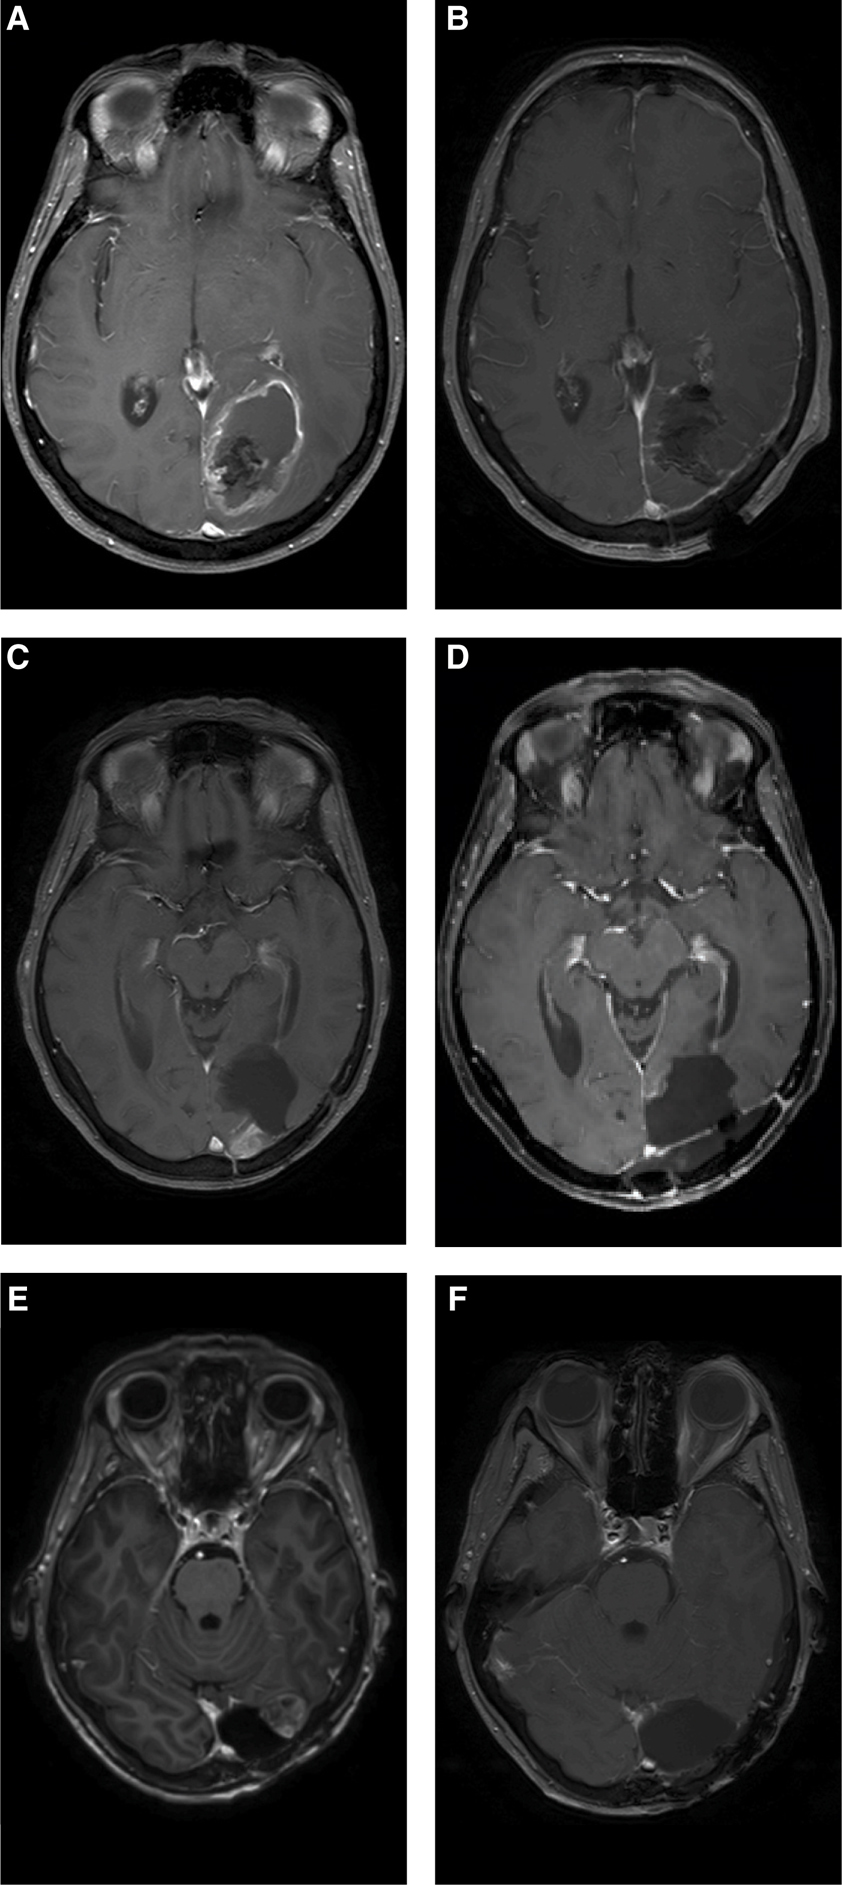

Fig 1

Figure 1 A 57-year-old lady was diagnosed with a left occipital glioblastoma (A), for which a total resection was performed (B). She was treated with standard radiotherapy, temozolomide chemotherapy, and experimental dendritic cell vaccination. An asymptomatic recurrence in the medial wall of the resection cavity was seen in a routine follow-up scan 16 months after the first surgery (C). A second total resection was performed (D), after which combined CCNU and bevacizumab was given in the EORTC 26101 study. A second asymptomatic local recurrence at the lateral side of the resection cavity was seen 14 months later (E), and again a total resection was performed (F). Nine months later she developed a multifocal progression, resistant to temozolomide. She died 42 months after the first surgery.